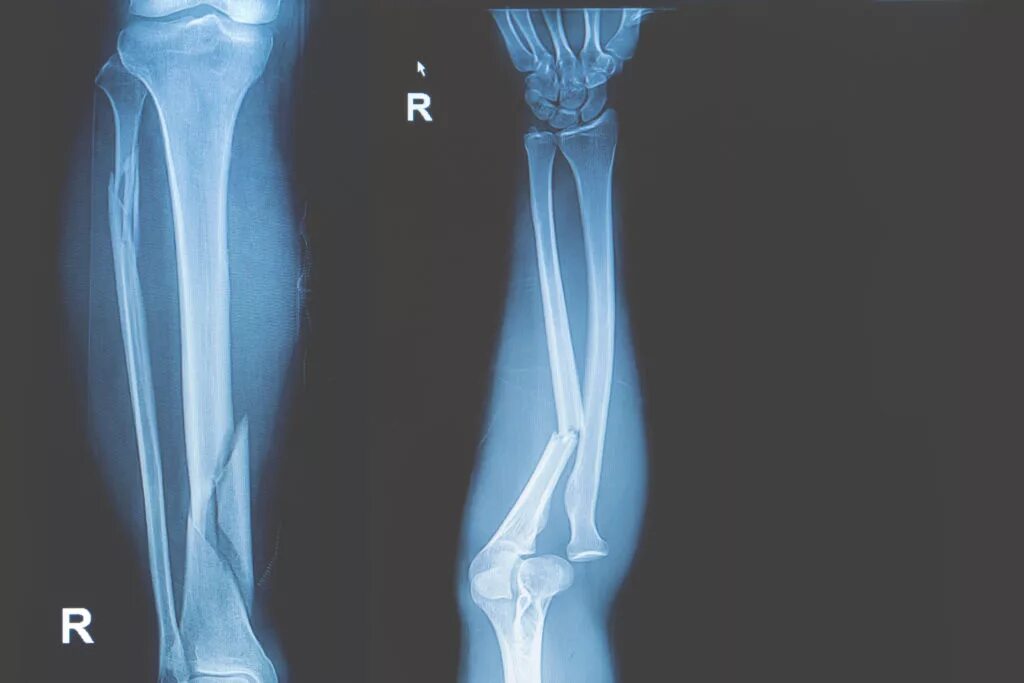

Снимок перелома со смещением